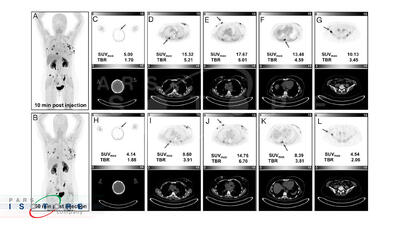

با افتتاح و بهرهبرداری از دستگاه پتاسکن (PET Scan) در هرمزگان، این استان به جمع معدود استانهای کشور پیوست که این خدمت تخصصی تصویربرداری پزشکی را با تعرفه دولتی به بیماران ارائه میدهند.

کردستان در ردیف ۶ استان برخوردار از دستگاه پتاسکن( تشخیص سرطان)

رئیس دپارتمان پزشکی هستهای پزشکی هستهای و تصویربرداری بیمارستان کوثر سنندج گفت: کردستان ششمین استاد کشور در دریافت دستگاه pet scan پیشرفته از نوع ۲۰۲۱ است که نشان از اهمیت و توجه به تجهیزات پزشکی پیشرفته در استان است.